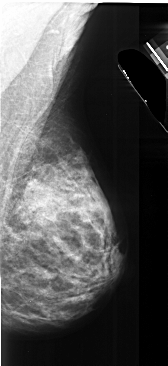

ics_version 1.0 filename A-1027-1 DATE_OF_STUDY 25 1 1993 PATIENT_AGE 48 FILM FILM_TYPE REGULAR DENSITY 4 DATE_DIGITIZED 7 1 1998 DIGITIZER DBA 21 SEQUENCE LEFT_CC LINES 4801 PIXELS_PER_LINE 2746 BITS_PER_PIXEL 16 RESOLUTION 42 OVERLAY LEFT_MLO LINES 5281 PIXELS_PER_LINE 2521 BITS_PER_PIXEL 16 RESOLUTION 42 OVERLAY RIGHT_CC LINES 4576 PIXELS_PER_LINE 2326 BITS_PER_PIXEL 16 RESOLUTION 42 NON_OVERLAY RIGHT_MLO LINES 5476 PIXELS_PER_LINE 2506 BITS_PER_PIXEL 16 RESOLUTION 42 NON_OVERLAY |